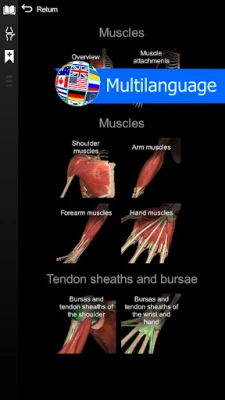

★ Support Spanish, French, German, Polish, Russian, Portuguese, Chinese and Japanese.

★ Muscles

★ Muscles